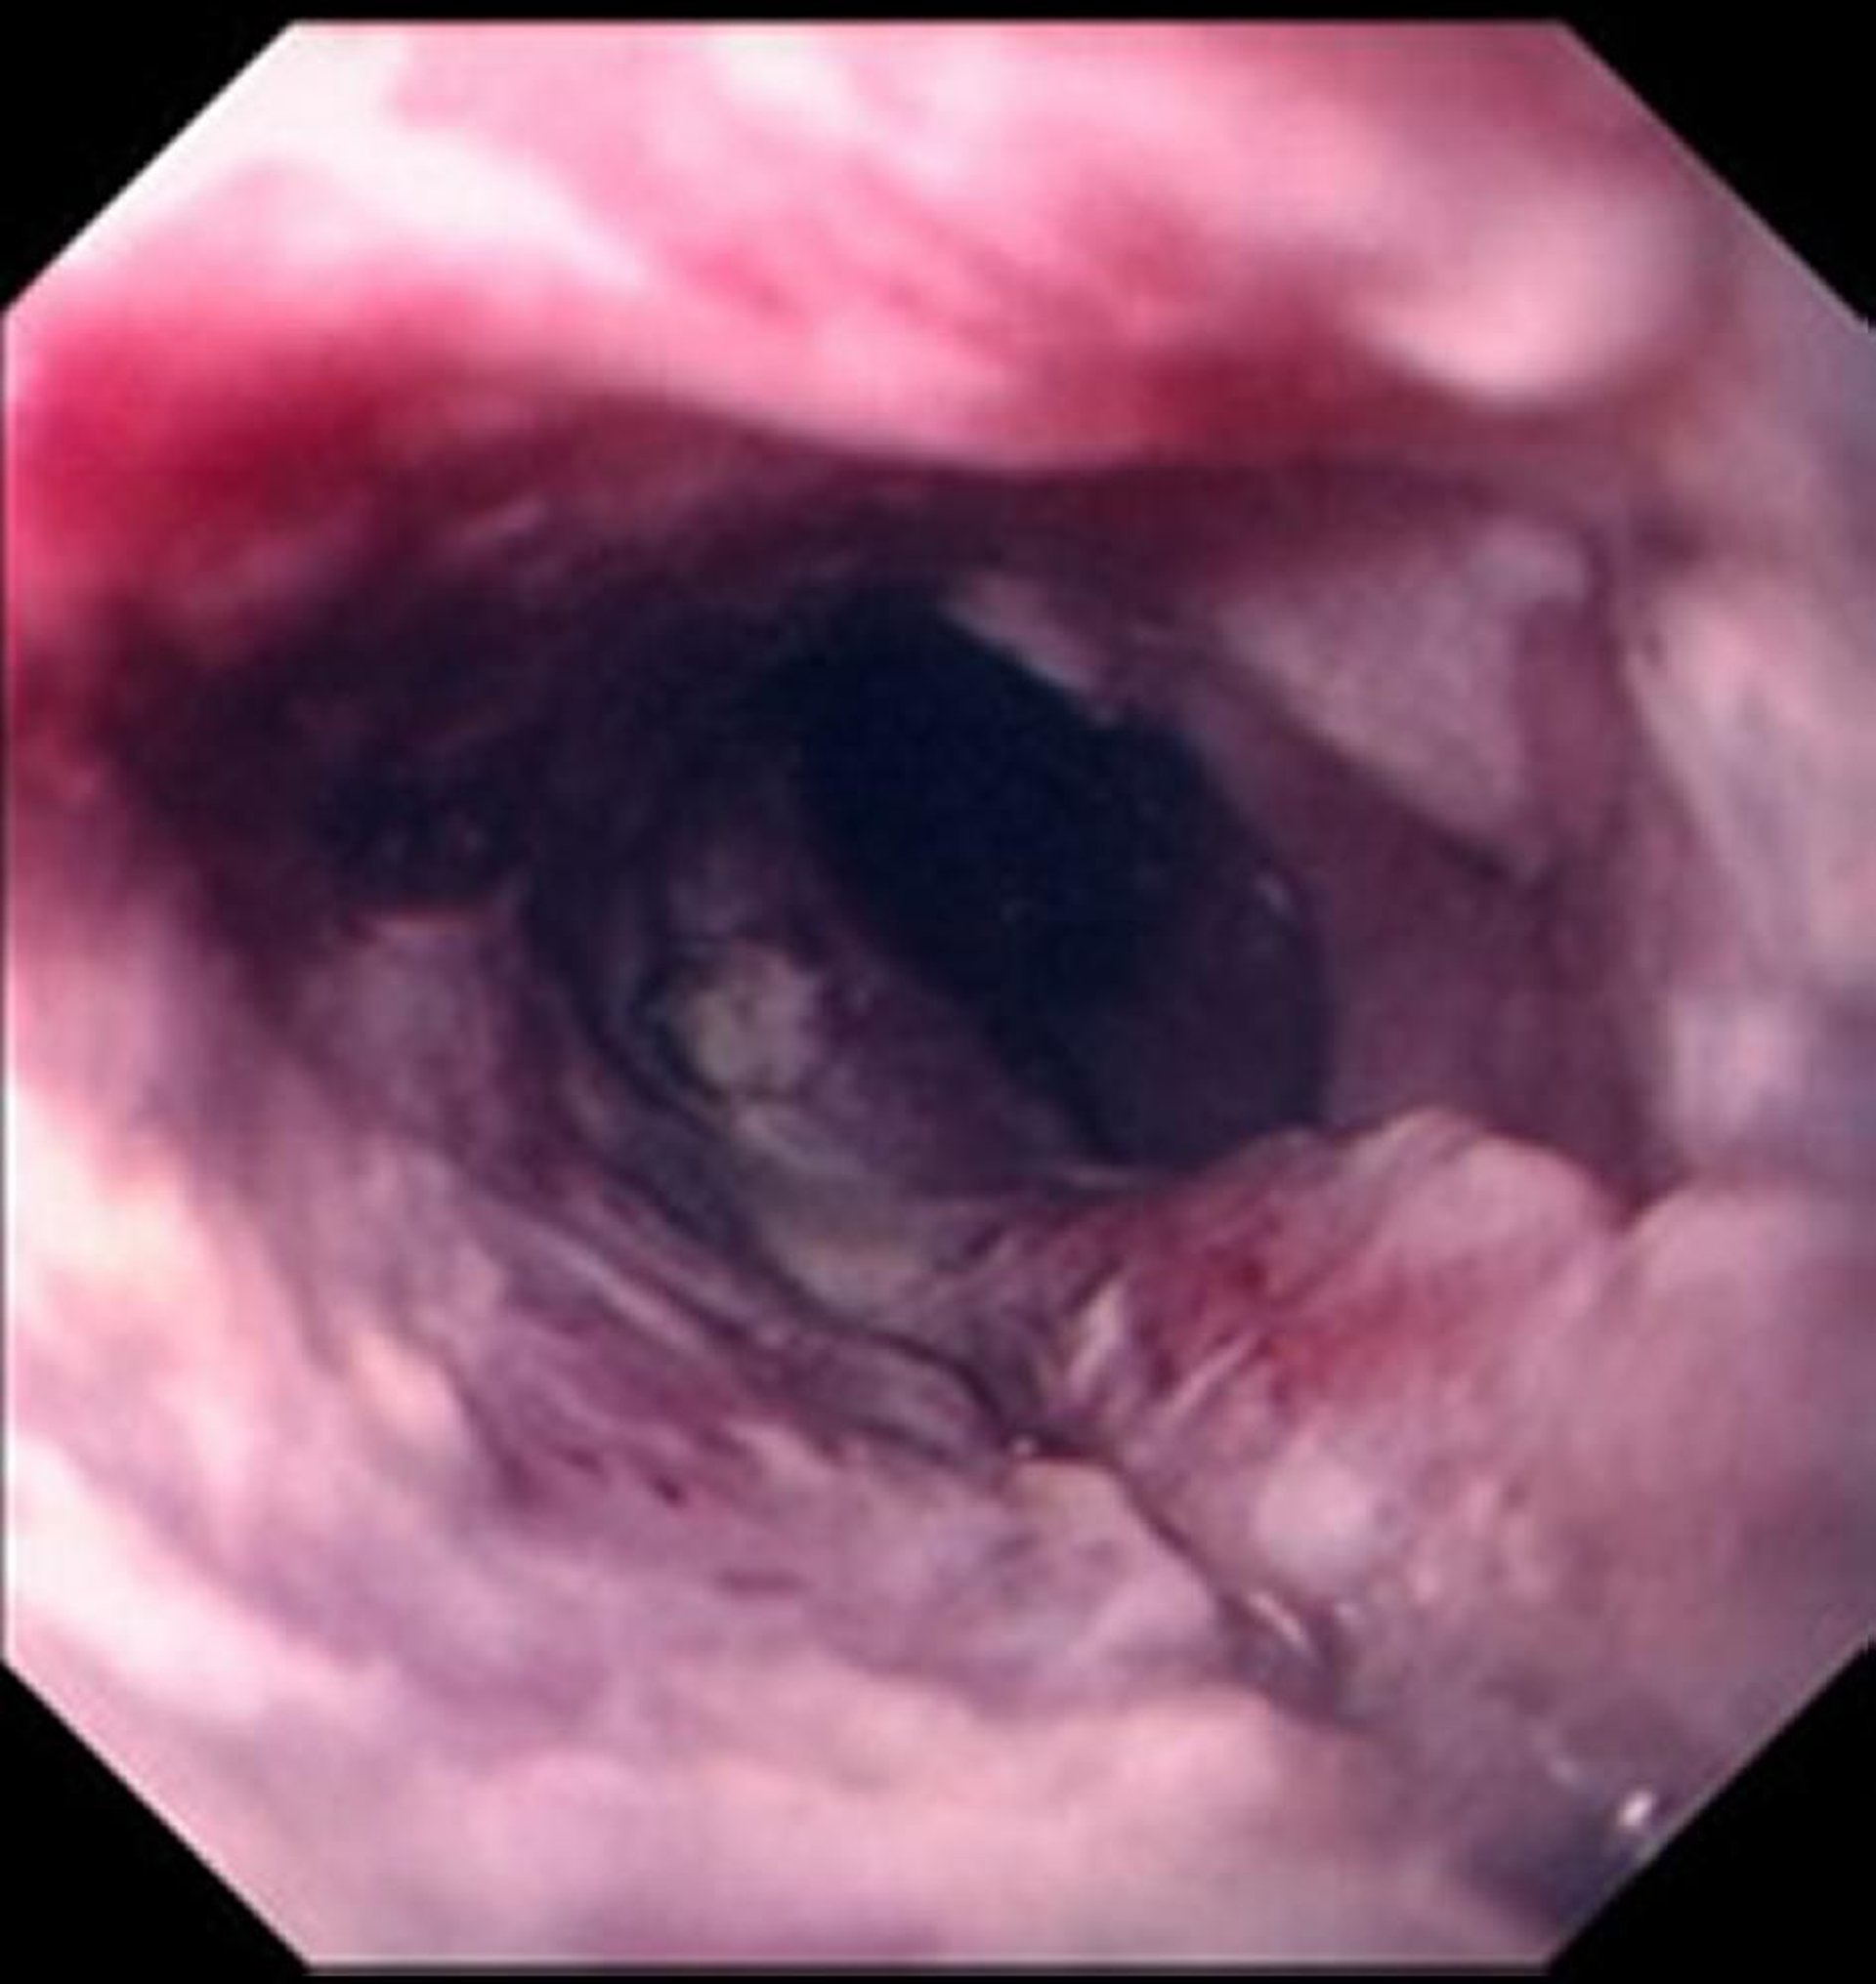

食道扁平上皮癌

扁平上皮癌は,典型的には潰瘍化した不整な腫瘤として現れ,食道内腔に障害をもたらす。